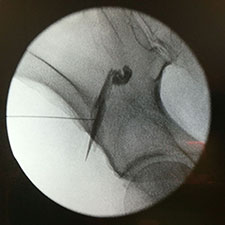

L'articulació coxofemoral també es pot infiltrar, ja sigui amb àcid hialurònic o amb corticoides.

La infiltració del múscul piramidal és una patologia freqüent pel que fa al dolor de la natja irradiat cap a l'extremitat inferior.